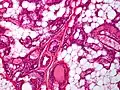

.jpg.webp) Small vessels in adipose tissue

Small vessels in adipose tissue.jpg.webp) Small vessels in adipose tissue

Small vessels in adipose tissue Small vessels in adipose tissue

Small vessels in adipose tissue Small vessels in adipose tissue

Small vessels in adipose tissue The vessels typically contain hyaline or fibrin (pictured) thrombi[3]